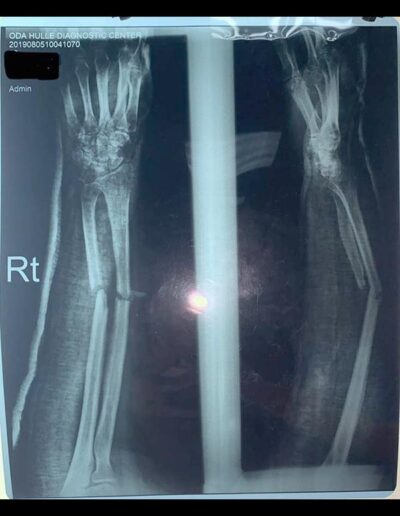

As a positive example, we would like to mention the case of 27-year-old Nabile. Six months ago, the patient suffered a forearm fracture in a car accident, which was treated in another hospital by plating the ulna and radius. Unfortunately, the material was removed far too early, a good five months later. The bone had not yet healed and a nonunion, as we call it, developed in the area of the fracture. This means that the bone at the fracture site does not have stable contact between the individual fragments and is therefore mobile and flexible, like a joint. This caused the young mother considerable pain and severely limited her ability to function as a mother of three small children. She therefore sought our help and came to our consultation hour. We agreed on surgical correction with implantation of bone material in the defect zone, which was taken from the patient's iliac crest during the same operation. We were able to perform the procedure on August 12, 2019. The X-ray now shows correct restoration of the two forearm bones with stabilizing bridging by two plates. After the operation, Céline began exercising the nearby joints through mobilization and provided instruction on self-therapy and correct positioning as part of daily physical therapy. The patient was extremely satisfied and grateful and, with our help, will be able to resume her duties as a mother and housewife. This case encourages us to continue our work here despite difficult conditions and to help people in need.